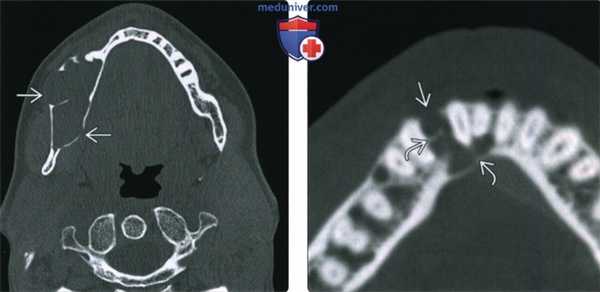

(Слева) При аксиальной КТ в коаном окне в теле нижней челюсти справа визуализируется большое многокамерное объемное образование экспансивного характера. Агрессивный характер этого образования проявляется в экспансивном воздействии на щечную и язычную кортикальную пластинку в совокупности с ее истончением и фокальным нарушением целостности.

(Справа) При аксиальной КТ в костном окне визуализируется небольшое объемное образование солидно-поликистозного характера, расположенное между боковым резцом и клыком. Обратите внимание, что в образовании, несмотря на его малый размер, присутствуют перегородки, а щечная кортикальная пластинка перфорирована.